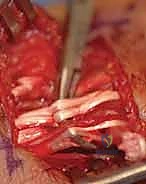

TECH FIG 4 • A–F. Flexor carpi radialis (FCR) and palmaris longus (PL) transfer for EDC reconstruction.